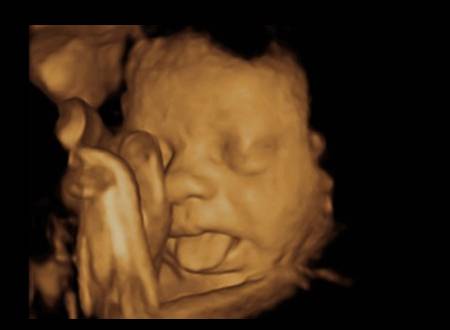

Bebelușul scoate limba și e simpatic foc!